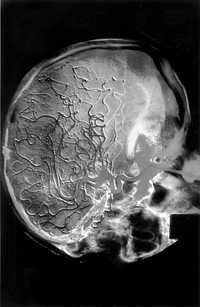

Investigadores de la Facultad de Medicina de la UNAM desarrollan un nuevo modelo para evaluar fármacos neuroprotectores en el tratamiento de la enfermedad vascular cerebral (EVC) isquémica, considerada la tercera causa de muerte en México y la primera de discapacidad motora.

La enfermedad, que puede ser ocasionada por la formación de un coágulo o un émbolo, se produce por la interrupción súbita del flujo sanguíneo de las arterias que irrigan al cerebro, lo que impide el suministro de oxígeno y nutrientes a las neuronas, que al morir causan los daños mencionados. Si el menoscabo inducido involucra áreas del cerebro que regulan la respiración, la frecuencia cardiaca o el metabolismo, el paciente puede caer en coma, o incluso morir.